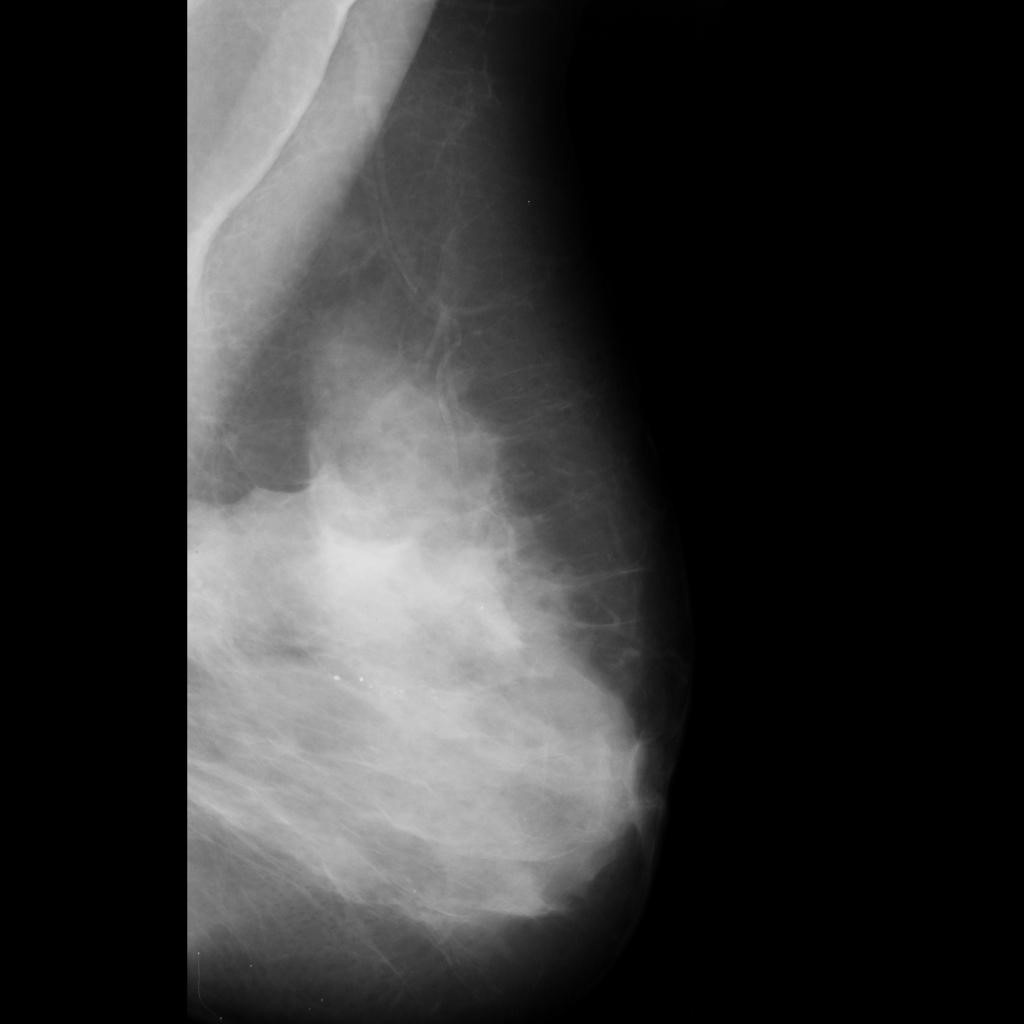

malignant